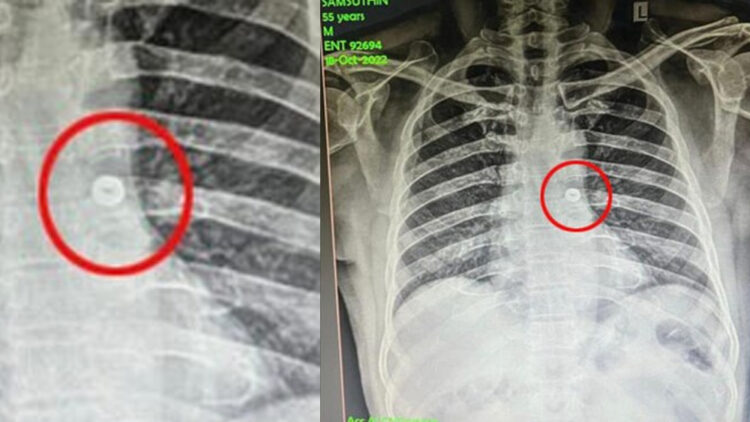

നട്ട് ഉള്ളിൽ പോയതോടെ ഷംസുദ്ദീൻ ചുമയ്ക്കാൻ ആരംഭിച്ചു. പിന്നാലെ ശ്വാസം എടുക്കാൻ ബുദ്ധിമുട്ട് അനുഭവിച്ചു. ഇതോടെ ഒപ്പം ഉണ്ടായിരുന്നവർ ഇയാളെ ആശുപത്രിയിൽ എത്തിക്കുകയായിരുന്നു. തുടർന്ന് ഷംസുദ്ദീനെ ഓട്ടോറൈനോലാറിംഗോളജി വിഭാഗത്തിൽ പ്രവേശിപ്പിച്ചു. നെഞ്ചിന്റെ എക്സ്-റേ എടുത്തപ്പോൾ ഇയാൾ വിഴുങ്ങിയ നട്ട് ശ്വാസനാളത്തിൽ കുടുങ്ങി ഇടതു ശ്വാസകോശത്തിലേക്ക് പോകുന്നതായി ഡോക്ടർമാർ കണ്ടെത്തി.

തുടർന്ന്, ഓട്ടോറൈനോലാറിംഗോളജി വിഭാഗം മേധാവി ഡോക്ടർ ശരവണൻ, അനസ്തേഷ്യോളജി വിഭാഗത്തിലെ അലിസുൽത്താൻ, മണിമൊഴി, സെൽവൻ, മദനഗോപാലൻ എന്നിവരടങ്ങുന്ന ഡോക്ടർമാരുടെ സംഘം എൻഡോട്രാഷ്യൽ ഉപകരണം ഉപയോഗിച്ച് ശസ്ത്രിക്രിയ നടത്തി. ഇതിലൂടെ ഷംസുദിൻ വിഴുങ്ങിയ ഇരുമ്പ് നട്ട് വിജയകരമായി പുറത്തെടുക്കുകയായിരുന്നു.